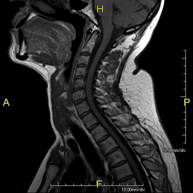

- Cervical spine MRI

This non-invasive diagnostic procedure uses an electromagnetic field and radio waves (from a transmitter and receiver) to acquire high-definition anatomical images of the cervical spine. It is a radiation-free procedure. Indicated for: trauma, spinal degeneration, hernias.